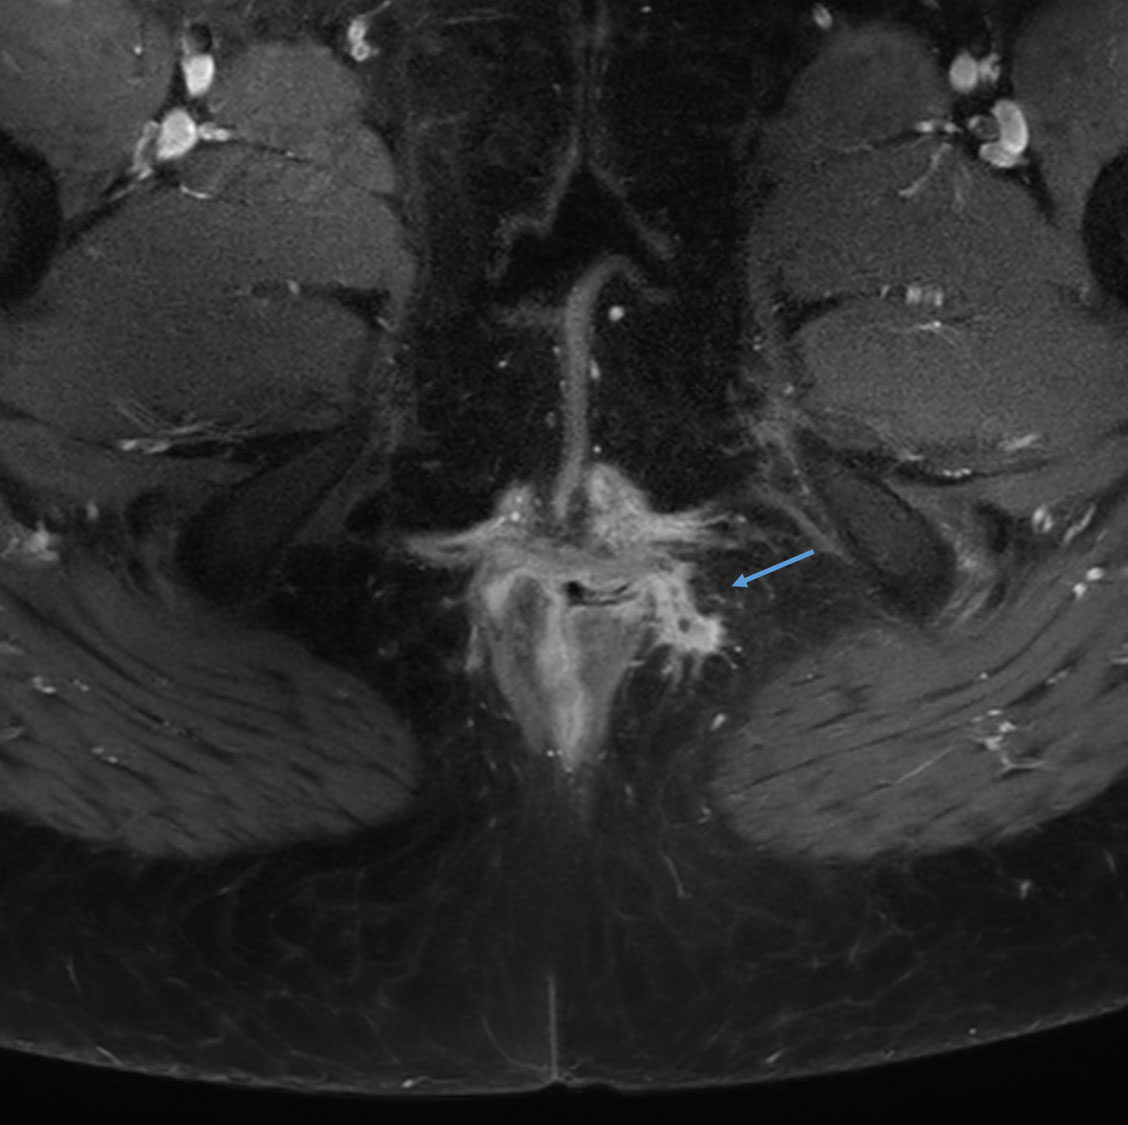

Axial T2w SPAIR

Axial T1w SPIR with gado